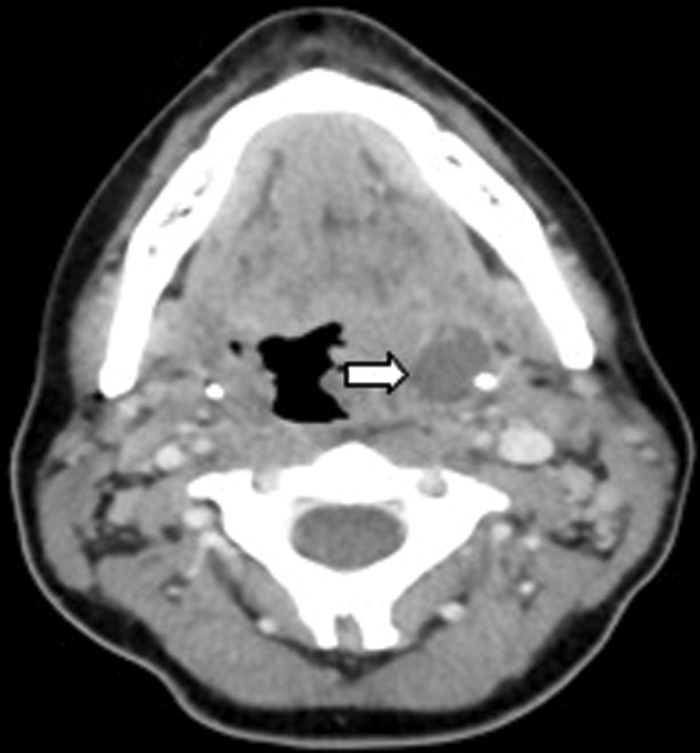

A 17-year-old male presented with a one week history of left otalgia and general malaise. Otoscopy was normal, but there was asymmetric left tonsillar enlargement. His inflammatory markers were raised suggesting sepsis.

CT (Figure 8) demonstrated a left peritonsillar abscess. In addition Figure 9 shows the patient to have bilateral calcified stylohyoid ligaments. Pharyngitis / tonsillitis are common causes of referred otalgia. Additionally calcification of the stylohyoid ligament greater than 28mm can compress the glossopharyngeal nerve causing dysphagia, tinnitus and otalgia, a collection of symptoms termed as Eagle’s Syndrome.

Figure 8: Contrast enhanced CT demonstrating a left peritonsillar abscess (white arrow).